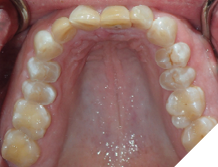

The majority of the orthodontic practices offer a period of “supervised retention” to their patients and communicates the customized retention recommendation with the patient’s general dentists. It is extremely important to work as a team to achieve long term clinical success in maintaining a functional bite and aesthetic smile. The general dentists continue to see their patients on a regular basis and have an opportunity to assess the orthodontic retainers and the bite after the supervised retention period is completed by the orthodontists. With great care, orthodontic retainers would serve for a long time (Fig. 1) without any major issues. However, in some cases, the failure to notice the clinical problems early on results in functional issues that would require a comprehensive orthodontic treatment to correct it (Fig. 2).

Fig. 1A

Fig. 1B

Fig. 1C